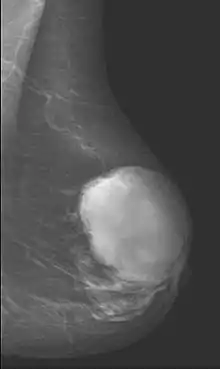

Phyllodes tumors (from Greek: phullon leaf), also cystosarcoma phyllodes, cystosarcoma phylloides and phylloides tumor, are typically large, fast-growing masses that form from the periductal stromal cells of the breast. They account for less than 1% of all breast neoplasms.

This is predominantly a tumor of adult women, with very few examples reported in adolescents. Patients typically present with a firm, palpable mass. These tumors are very fast-growing, and can increase in size in just a few weeks. Occurrence is most common between the ages of 40 and 50, prior to menopause. This is about 15 years older than the typical age of patients with fibroadenoma, a condition with which phyllodes tumors may be confused. They have been documented to occur at any age above 12 years.

Phyllodes tumors are a fibroepithelial tumor composed of an epithelial and a cellular stromal component. They may be considered benign, borderline, or malignant depending on histologic features including stromal cellularity, infiltration at the tumor's edge, and mitotic activity.[1] All forms of phyllodes tumors are regarded as having malignant potential. A large series from the M.D. Anderson Cancer Centre reported the incidence of each as benign (58%), borderline (12%), and malignant (30%). Malignant phyllodes tumours behave like sarcomas and can develop blood-borne metastases. Approximately 10% of patients with phyllodes tumours develop distant metastases and this can go up to 20% in patients with histologically malignant tumours.[2] The commonest sites for distant metastases are the lung, bone, and abdominal viscera. Rare sites of metastasis, such as to the parotid region, have also been described.[3]